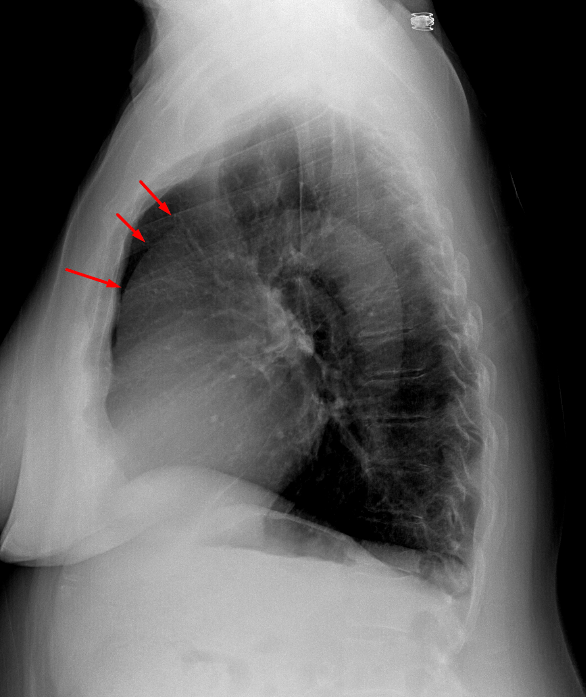

Age: 77

Sex: Female

Indication: Fever

Sample ReportAscending aortic aneurysm. Recommend chest CTA for further evaluation.

Otherwise, no evidence of acute cardiopulmonary disease.